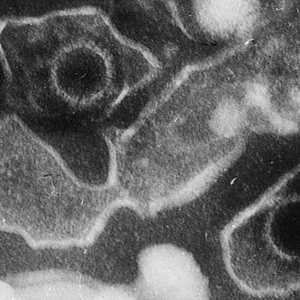

EB 病毒(左上和右下)电镜照片。图片来源:Liza Gross - (2005) Virus Proteins Prevent Cell Suicide Long Enough to Establish Latent Infection。 PLoS Biol 3(12): e430 DOI: 10.1371/journal.pbio.0030430,CC BY 2.5,https://commons.wikimedia.org/w/index.php?curid=861856